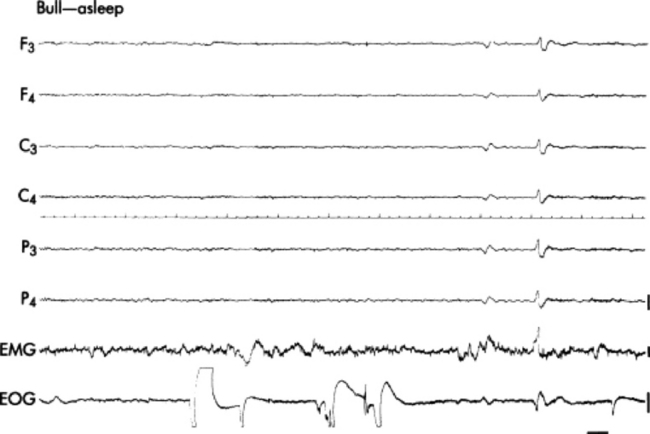

Antemortem diagnostic tests include radiographs of the skull (for tumors that spread locally and some metastatic tumors), and electroencephalography (EEG) to elucidate brain dysfunction.1421 Where available, CT or MRI can greatly facilitate diagnosis, but limited availability and considerations of cost restrict their use in most cases.1428,1430-1432